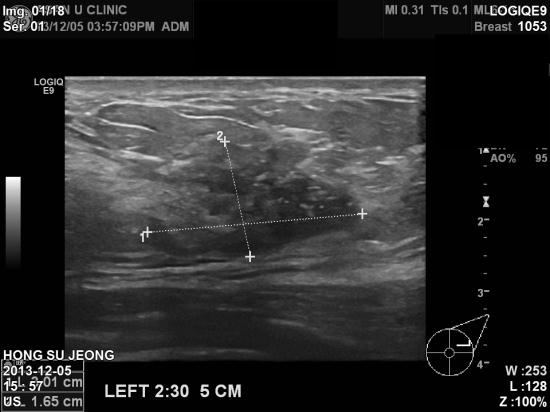

엑스레이와 초음파상에도 석회화와 함께 이상소견있어 조직검사 결과

침윤성유방암 및 겨드랑이 임파절 전이성 유방암으로 진단

되어 치료 예정이십니다.